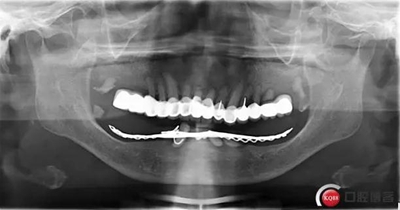

全口種植一例 科貿(mào)嘉友收錄

患者因上口瓷牙松動,下牙托戴不穩(wěn)求診。

全過程約70日。因下牙槽骨較低,事前拍全景片。至今完成修復3個月,咀嚼效果良好。